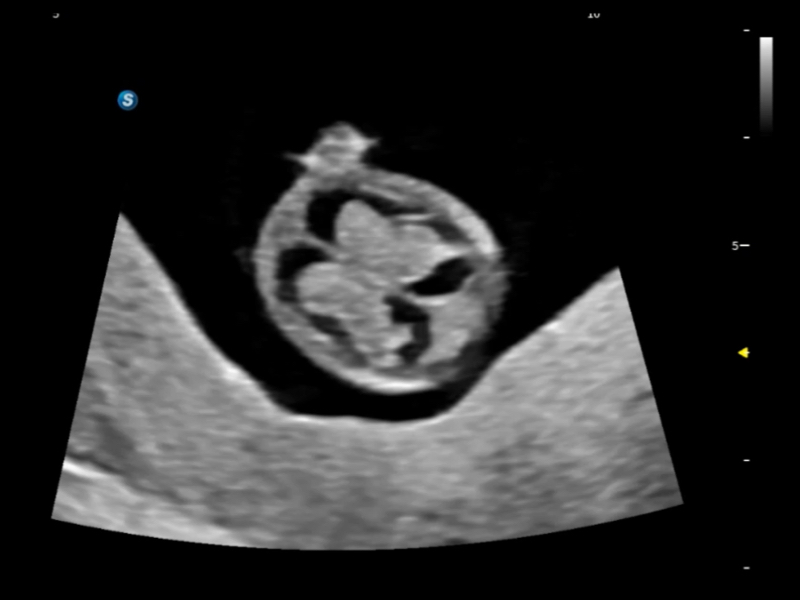

通过光照模型,使二维血流显示出立体的效果,增加血流的敏感性、成束性,减少外溢。可以和其他不同的血流技术联合使用,融合不同技术的优势。轻松应对微小血管,增强血流的立体效果,提升视觉敏感性。

通过创新的Matrix E自适应滤波算法,能有效滤除软组织和噪声信号,最大限度保留超低速微细血流的信号;结合超长时间域算法,极大提升细微血流的敏感性和空间分辨率,更真实的反应组织、包块的血流灌注情况。